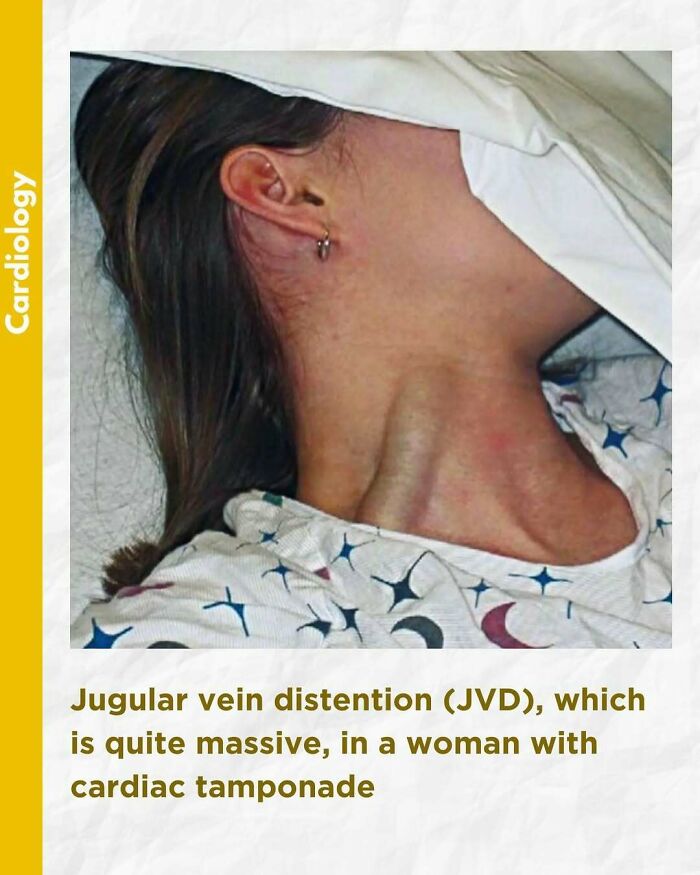

An elevated jugular venous pressure (JVP) is the classic sign of venous hypertension (e.g. right-sided heart failure). JVP elevation can be visualized as jugular venous distension, whereby the JVP is visualized at a level of the neck that is higher than normal. The jugular venous pressure is often used to assess the central venous pressure in the absence of invasive measurements (e.g. with a central venous catheter, which is a tube inserted in the neck veins).